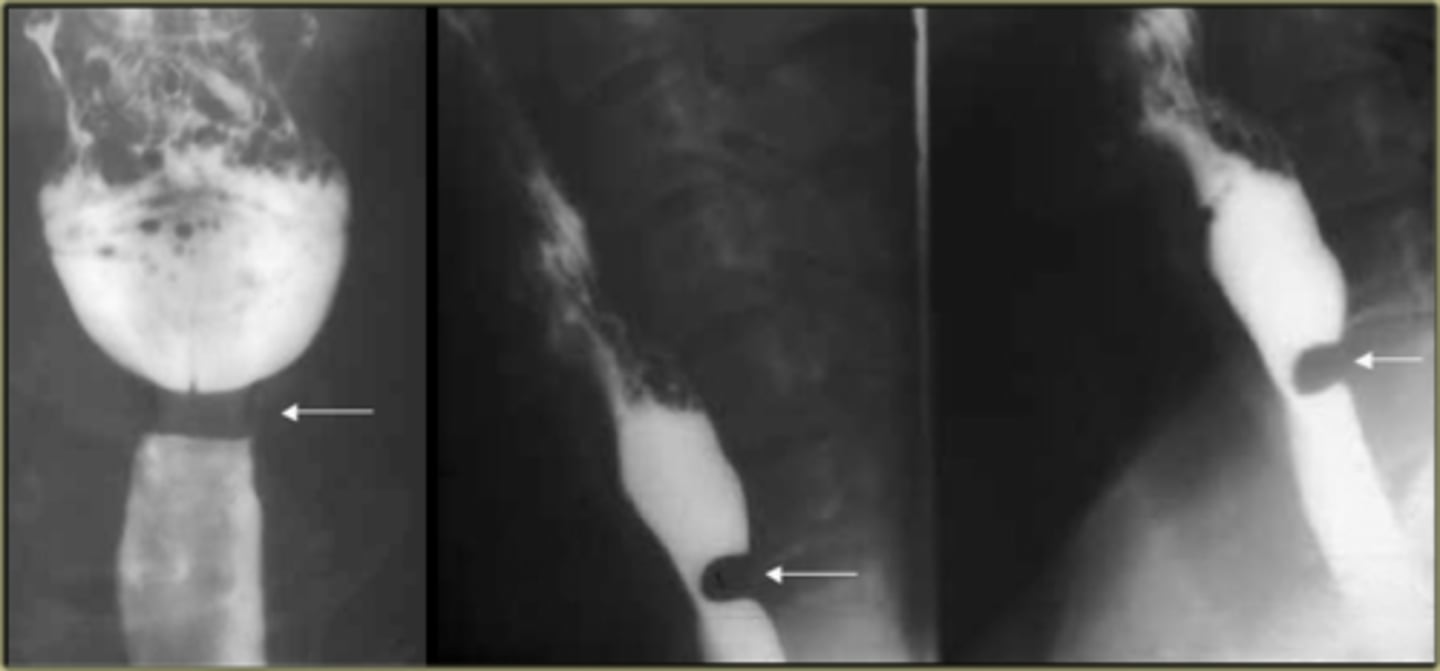

Esophageal diverticula.

(A)WHITE ARROW:

localized weakness in the posterior wall of the hypopharynx;

in the mid-esophagus from extrinsic disease such as tuberculosis that causes fibrosis, which pulls on the esophagus, forming a traction diverticulum (dotted white arrow)

DOTTED WHITE ARROW:

traction diverticulum. fibrosis pulling on the esophagus.

B: BLACK ARROW:

Epiphrenic diverticulum, just above the diaphgram in the distal esophagus.

(C). Only the traction diverticulum is a true diverticulum in that it has all layers of the esophagus involved; the Zenker and epiphrenic are false or pseudodiverticula because the mucosa and submucosa herniate through a defect in the muscular layer. The Zenker diverticulum is the only one of the three that typically produces symptoms.